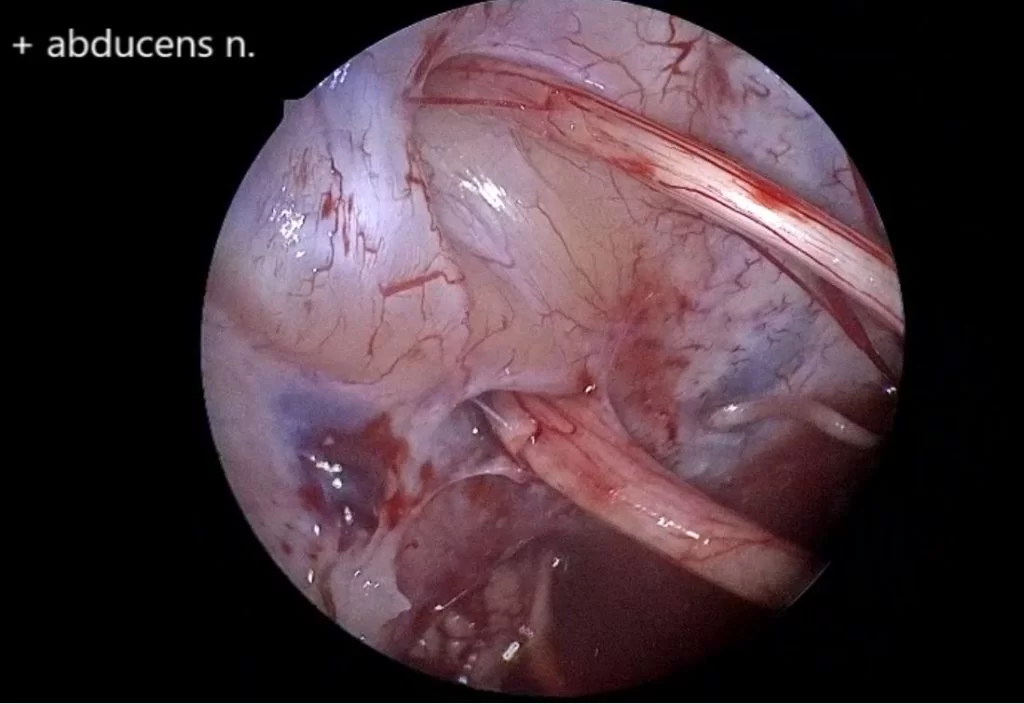

Διενεργήθη οπισθοσιγμοειδική οστεοπλαστική προσπέλαση και ολική εξαίρεση της βλάβης.

Σε τέτοιες βλάβες είναι εξαιρετικά σημαντική η εμπειρία του νευροχειρουργού στη χειρουργική των όγκων της βάσης κρανίου. Σημαντικά βοηθήματα είναι ο διεγχειρητικός νευροφυσιολογικός έλεγχος και η χρήση του ενδοσκοπίου προκειμένω να ελεγχθούν ακόμα και “κρυφά” σημεία του χειρουργικού πεδίου.